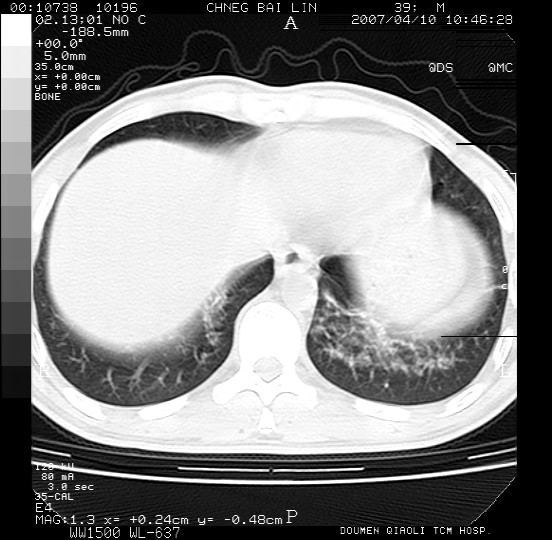

男,39岁。10天前自觉感冒,曾输液一次内容不详曾有吸毒史。现有咳嗽、咳痰胸闷。

双肺弥漫性网状、磨玻璃样病灶,边界不清。有吸毒史。首先考虑机遇性肺部感染。

两肺弥漫分布的网状毛玻璃状阴影,边缘模糊不清,纵隔未见明显淋巴结肿大

诊断:机遇性肺部感染

鉴别诊断:1特发性肺纤维化,主要部位在两肺下叶胸膜下网状,毛玻璃状及蜂窝状阴影,临近胸膜增厚,该病征象不太符合